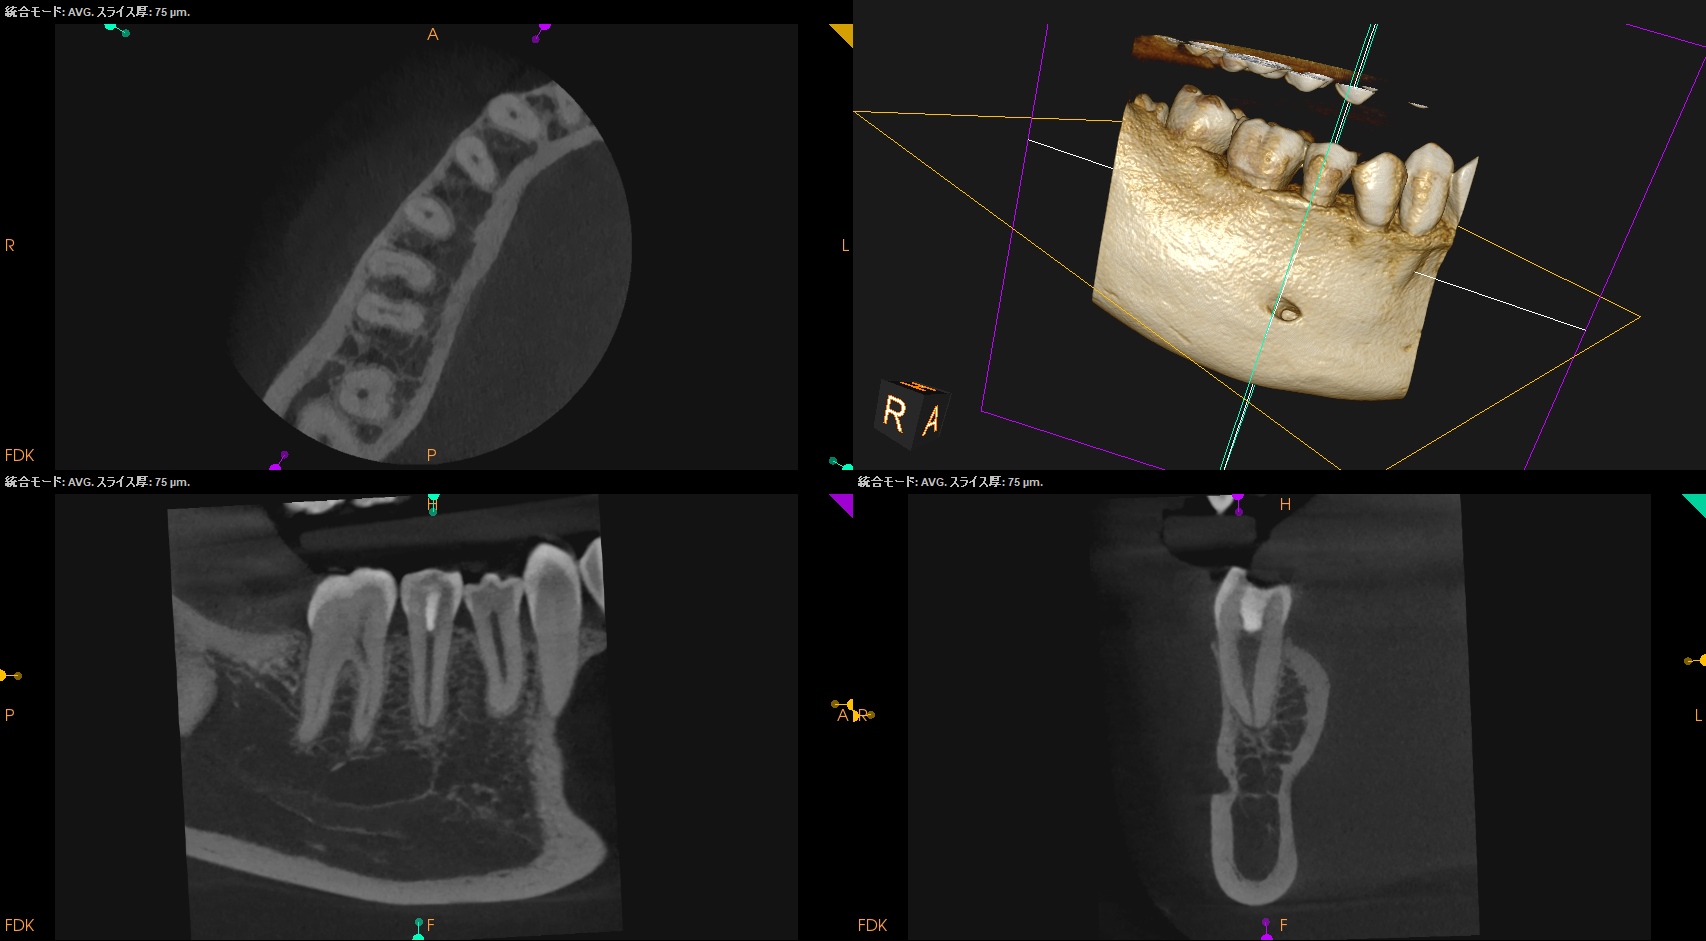

根管充填後にPA, CBCTを撮影した。

問題はないだろう。